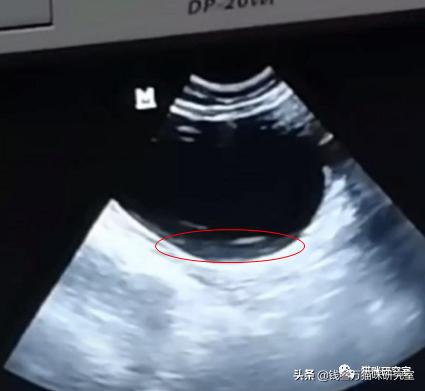

B超图,沉淀在膀胱中泥沙状的结晶: